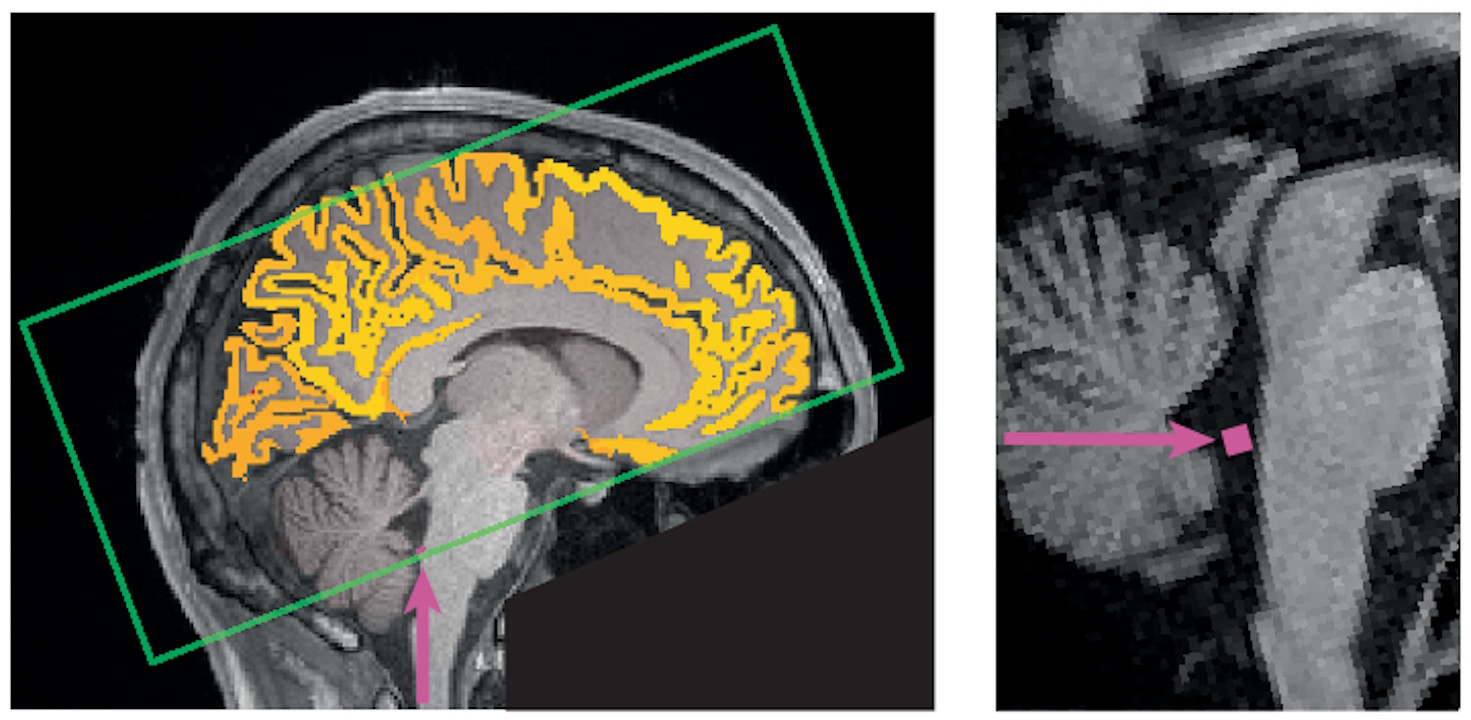

Знімки магнітно-резонансної томографії мозку одного з учасників дослідження, за якими визначали потік спинномозкової рідини. Yang et al. / Nature Neuroscience, 2025

Дослідження проводили за участі 26 добровольців, яким проводили електроенцефалограму й МРТ мозку та тести на увагу після ночі здорового сну та після безсонної. Як виявилося, після безсонної ночі в учасників періодично погіршувалася увага, що збігалося з хвилями спинномозкової рідини, яка відтікала з мозку. Ці хвилі мали такий самий характер, як хвилі спинномозкової рідини під час повільної фази сну, і набагато частіше траплялися саме після безсонної ночі, а не здорового сну.

У середньому в учасників увага погіршувалася за дві секунди до хвилі спинномозкової рідини з мозку та покращувалася за секунду після хвилі цієї рідини в мозок. Це може свідчити про компроміс між підтриманням базових функцій мозку та більш енергозатратними процесами, такими як утримання уваги на чомусь одному. Крім хвиль у мозку, періоди погіршення уваги також збігалися в часі зі звуженням зіниць і сповільненням серцевого та дихального ритму. Це може вказувати на спільний механізм, який регулює відновлення різних систем організму після безсонної ночі.